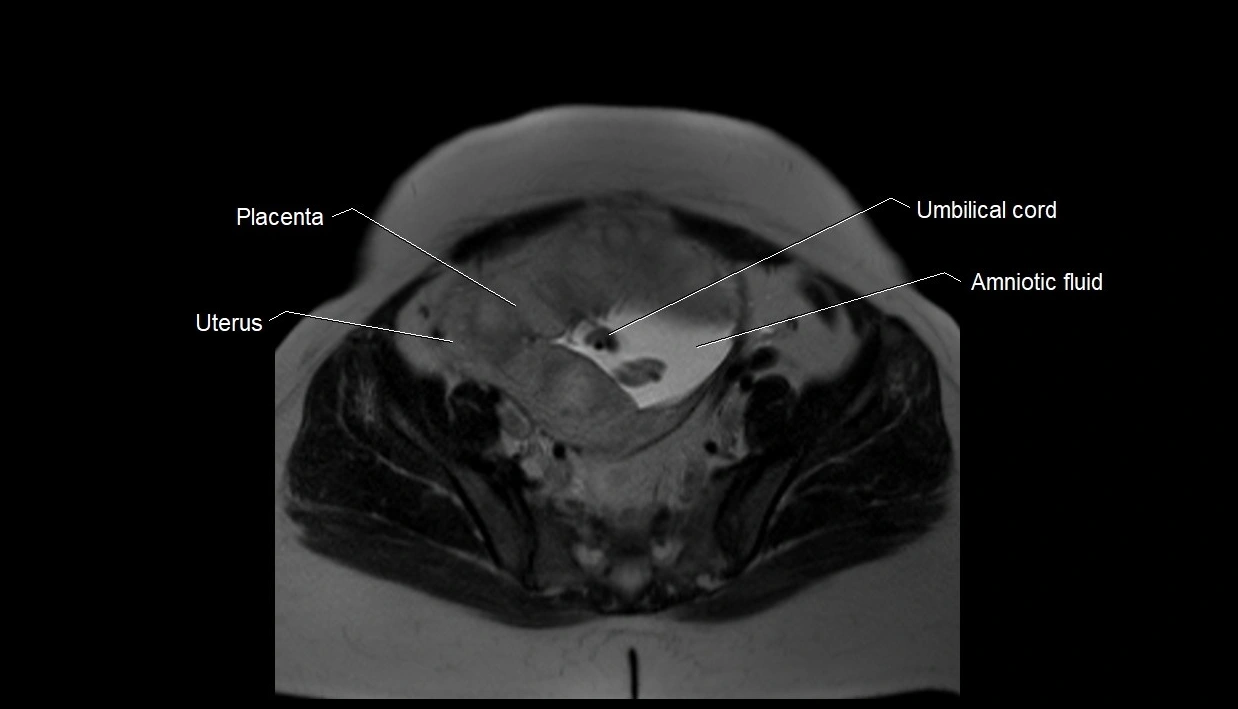

Amniotic fluid is the protective liquid surrounding the fetus within the amniotic sac. It plays an essential role in cushioning the fetus, enabling fetal movement, maintaining temperature stability, and allowing for normal lung and musculoskeletal development.

The volume and composition of amniotic fluid change throughout pregnancy. It is mainly derived from maternal plasma in early pregnancy, while in later stages, it consists largely of fetal urine, lung secretions, and transmembrane exchanges.

MRI Appearance

T2 HASTE (T2 GRE):

• Amniotic fluid shows very bright hyperintense signal

• Provides natural contrast against fetus and placenta

• Small particles (vernix) may appear as scattered hypointense foci within bright fluid